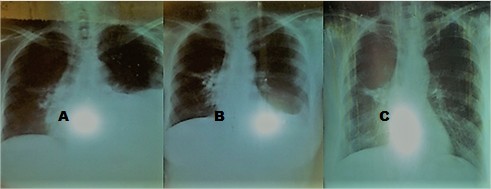

A) Inicial: Opacidad tumoral parahiliar derecho y pleuresía izquierda de mediana cuantía

B) Postoracocentesis, 2 días posteriores a la nefrostomía percutánea izquierda: opacidad tumoral parahiliar derecho y disminución de la pleuresía izquierda de mediana cuantía

C) 7 días posteriores a la nefrostomía percutánea izquierda: opacidad tumoral parahiliar derecho y desaparición de la pleuresía izquierda (fig. 2)